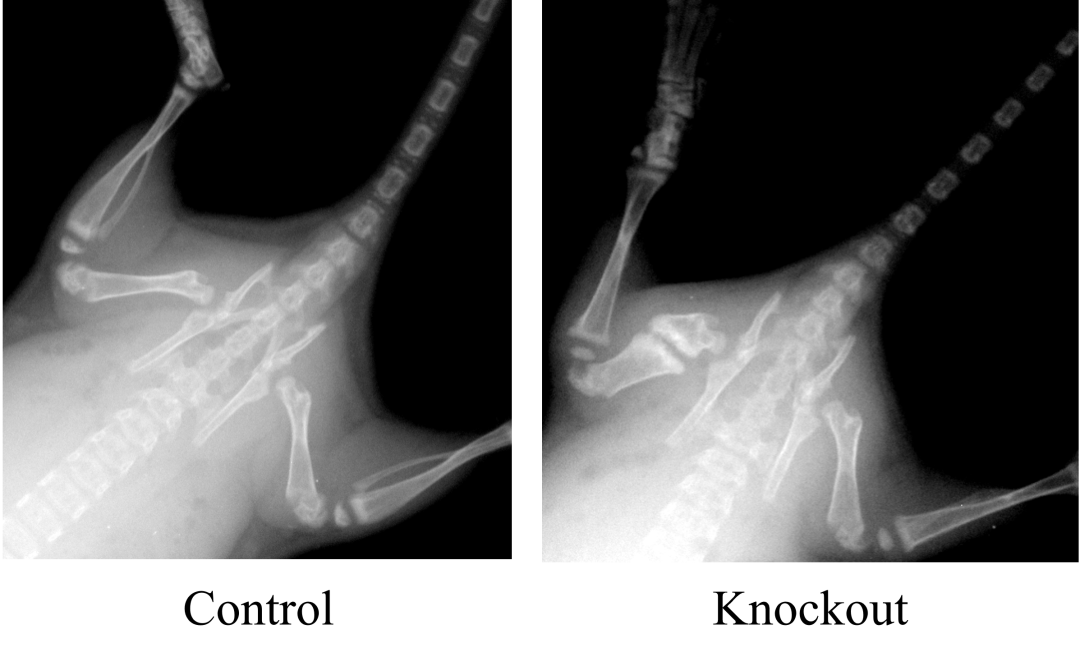

X光成像在骨科相关研究的应用

3. X光成像 (X-ray Imaging)

原理:基于X射线穿透物质时发生的衰减原理。不同密度的组织(如骨骼、软组织、肺部气体)对X射线的吸收能力不同。高密度组织(如骨骼)吸收更多X射线,低密度组织(如脂肪、肺)吸收较少。当X射线束穿过动物身体后,未被吸收的X射线投射到探测器(如平板探测器或胶片)上,形成反映组织密度差异的投影图像(如X光平片)。在计算机断层扫描(Micro-CT)中,动物在旋转平台上接受多角度X射线投影,计算机重建出横断面图像或三维结构图像。

特点:提供高分辨率的解剖结构信息,特别擅长显示骨骼结构、肺部病变、体内植入物位置等。成像速度快。但通常不涉及特异性的分子或细胞标记(主要用于结构成像),软组织对比度相对较低(除非使用造影剂),涉及电离辐射。

3. X光成像

X-Ray成像

样本准备:麻醉固定,或注射碘海醇等造影剂

参数设置:电压40-60 kV,电流0.5-1 mA(小动物)

图像采集:曝光时间0.1-5 s,多角度拍摄(可选CT 3D重建)

三维重构:通过Micro-CT获取10-50 μm分辨率体数据